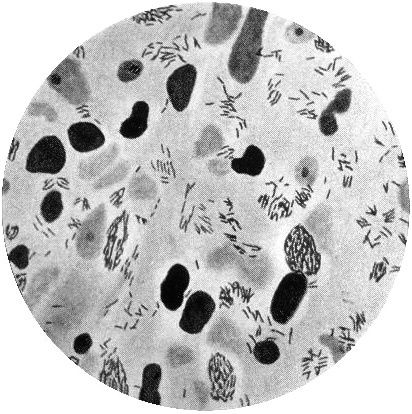

Nur sieben Jahre, nachdem die Kolonie eröffnet wurde, isolierte der norwegische Wissenschaftler Gerhard Armauer Hansen das für die Lepra verantwortliche Bakterium: Mycobacterium leprae. Es war das erste Bakterium, von dem nachgewiesen werden konnte, dass es eine menschliche Krankheit verursachte. Kurz danach isolierte der deutsche Physiker Robert Koch die Bakterien, die für Milzbrand, Tuberkulose und Cholera verantwortlich sind. Die Isolation dieser Bakterien widerlegte die Gifthauch-Theorie, nach der die Krankheiten durch das Einatmen von mit Fäulnis durchsetzter Luft ausgelöst wurden.